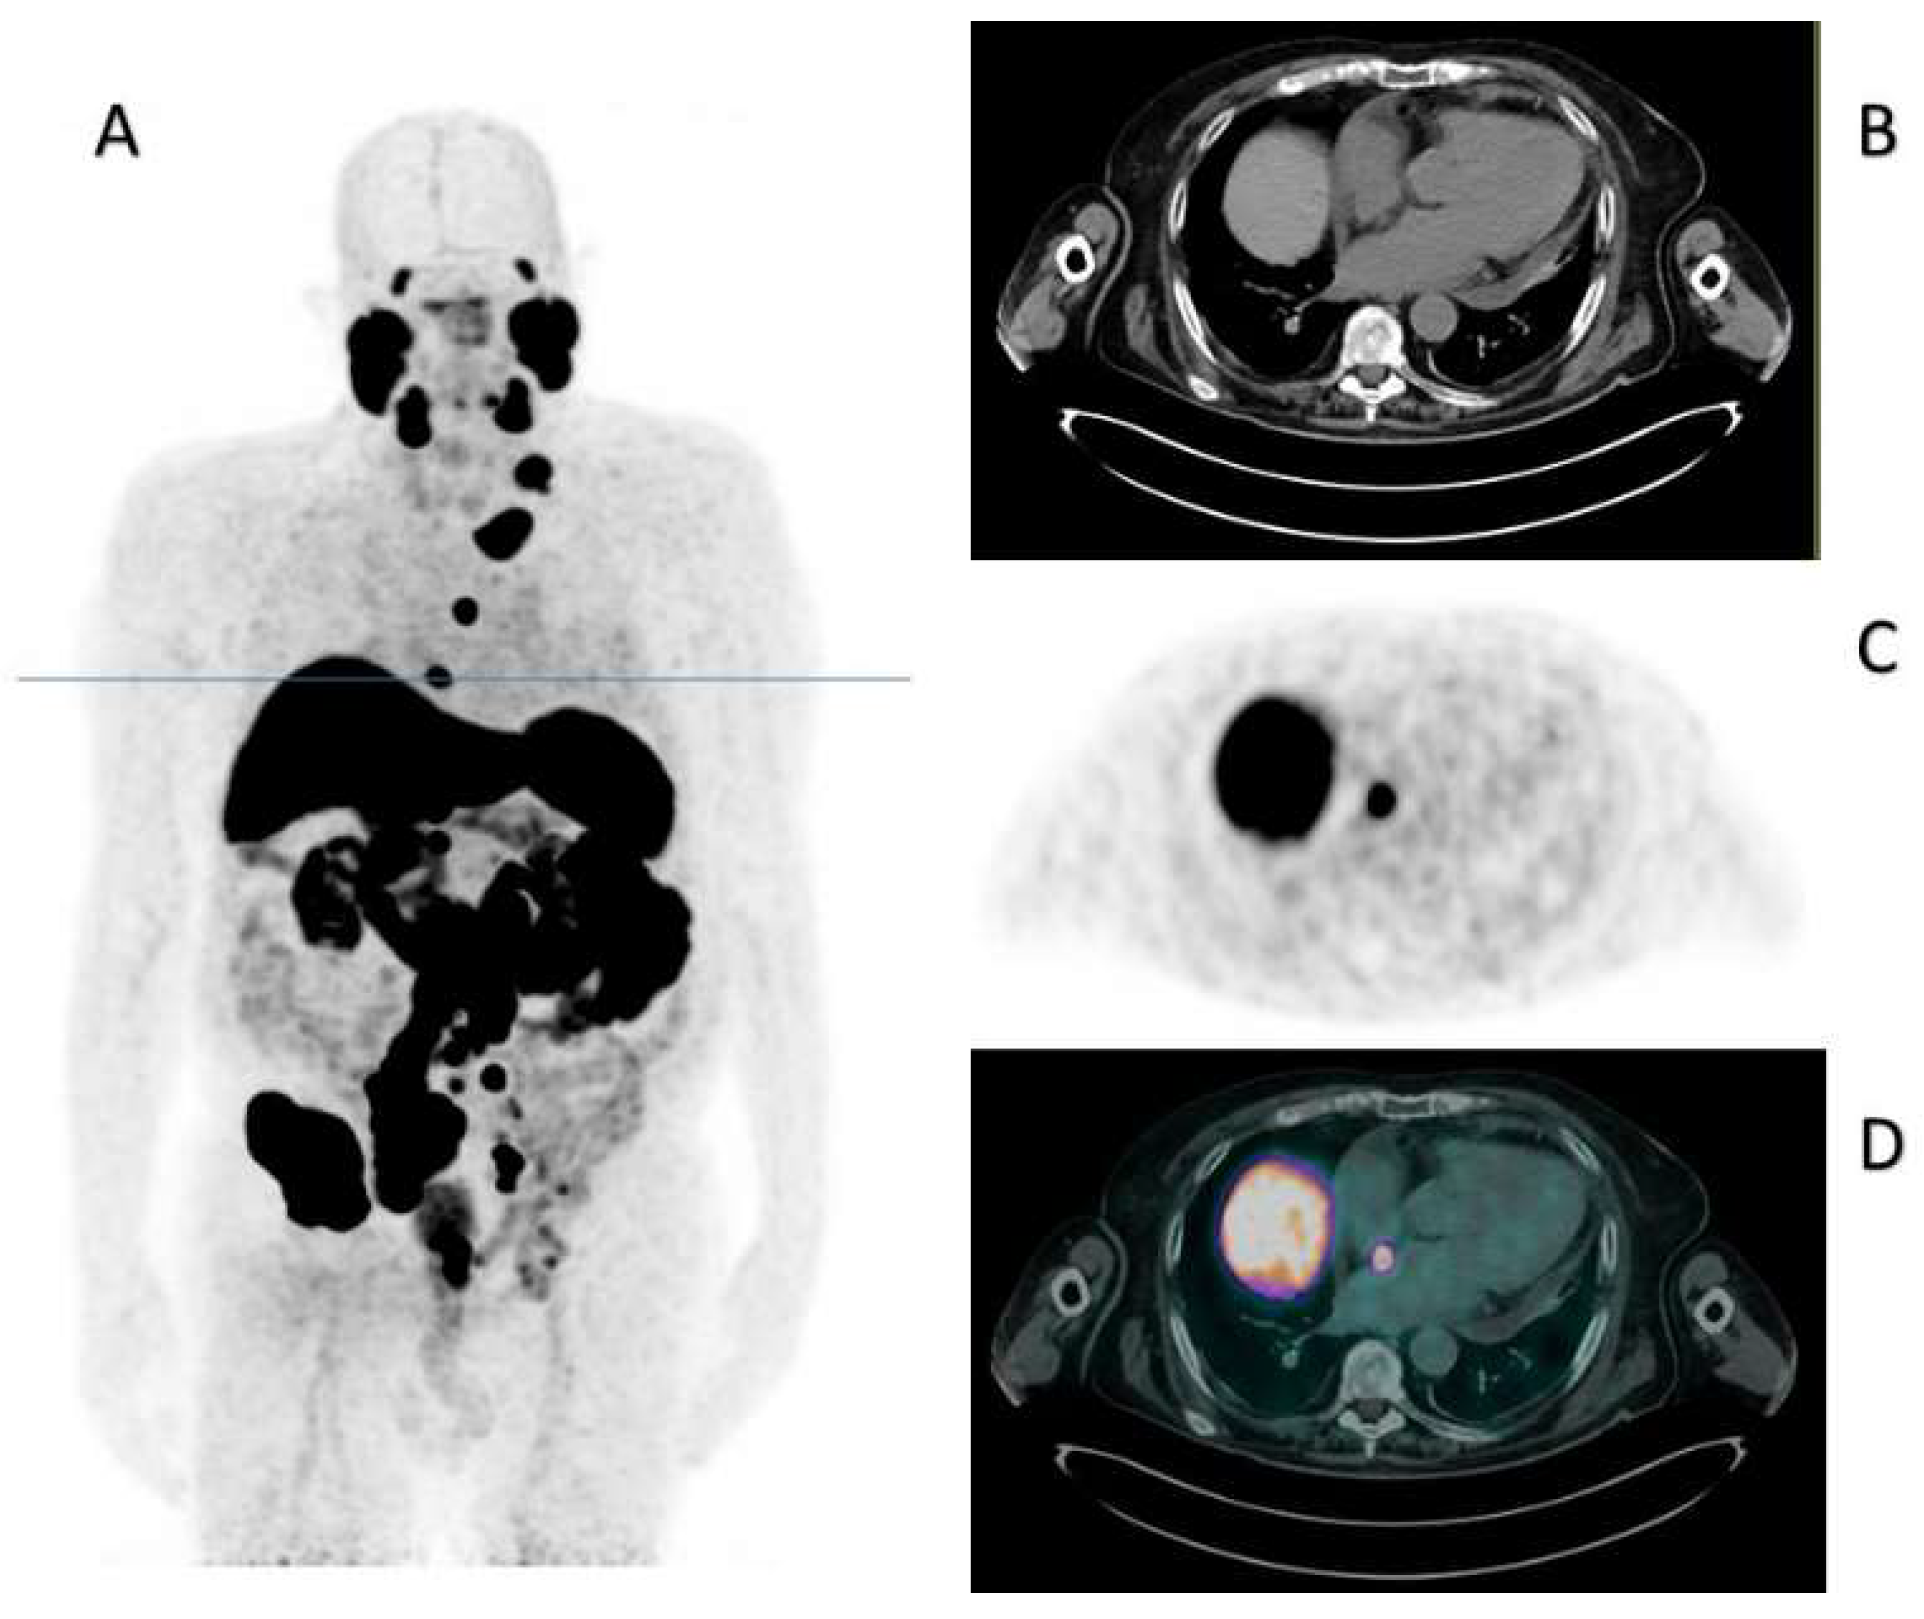

Gandini, A.; Bauckneht, M.; Sofia, L.; Tomasello, L.; Fornarini, G.; Zanardi, E. Cardiac Metastasis from Prostate Cancer: A Case Study Underlying the Crucial Role of the PSMA PET/CT. Diagnostics 2023, 13, 2733. https://doi.org/10.3390/diagnostics13172733